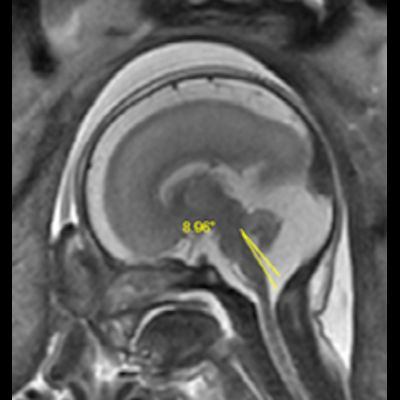

- B) Aksiyel ve sagittal T2A görüntülerde gyrus ve sulkuslarda azalma mevcut olup korteks kalınlaşmış görünümde ve operkulizasyon ayırt edilememiştir. Korteks beyaz cevher ayrımı zor seçilmektedir (ok) Ekstraaksiyel BOS mesafesi artmış görünümdedir (ok). Yapılan ölçümlerde; tegmentovermian açı :8 derece (ok) serebellar vermis boyutları kraniokaudal: 16 mm, aksiyel: 5,5×8,5 mm (ok) ölçülmüş olup BPD:27w ile uyumlu olan fetüste haftasıyla uygun olarak değerlendirilmiştir.